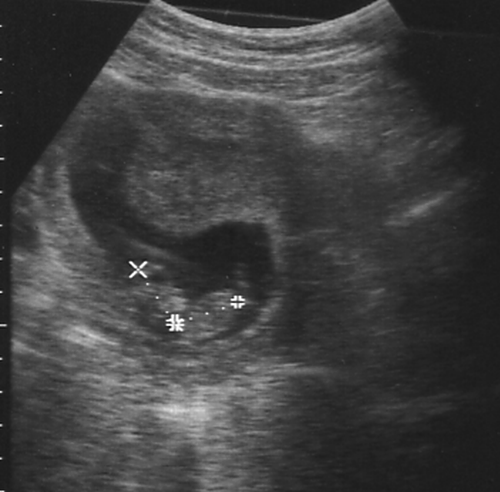

Do you like my photo? I don't think they got my best side! If you look carefully you can see my head and body, but the rest is a bit hazy. I'm almost 13 weeks old and doing fine. They say that I'll be ready for the big wide world at the end of October, but we'll have to wait and see what I feel like – I might wait till November!

When I had my photo taken last week I did a little dance for Mummy and Daddy so that they could see that I was happy, and my heart was beating strong.